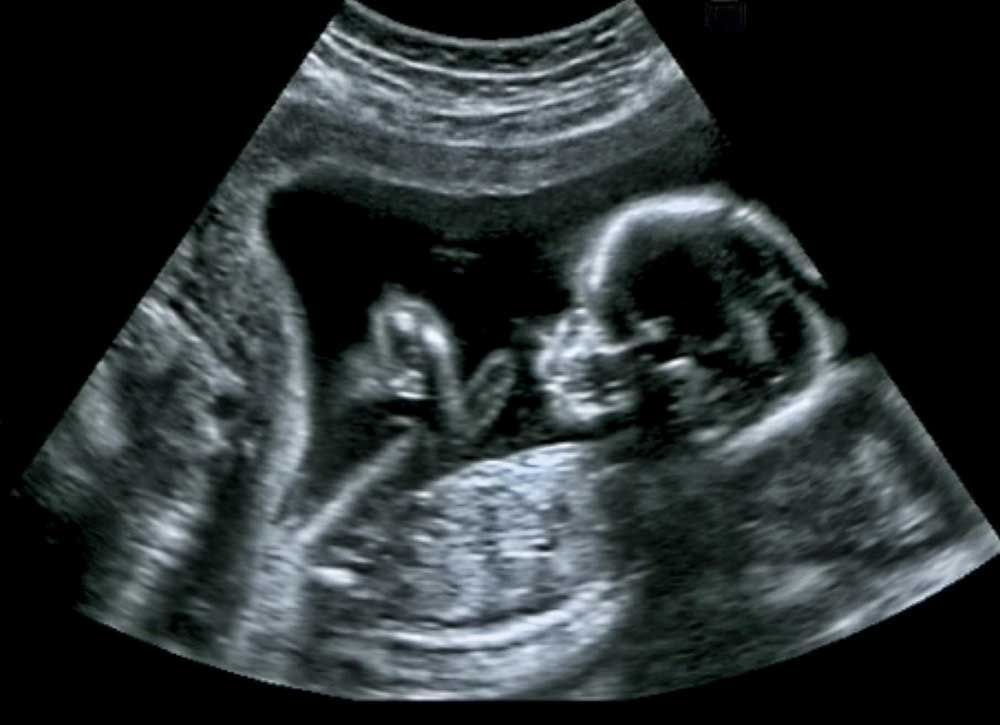

Ultrasonography is indicated in various conditions. The advantages of ultrasound are: - Can be performed at bedside i.e., portable - No ionizing radiations - Soft-tissue visualization - Non-invasive - Helps in guiding wires or drains - Amount and flow of blood in vessels - Helps visualize blockage in vessels e.g., atherosclerosis in carotid arteries - Can help visualize blood clots - Differentiation of solid and cystic masses - Essential for determining the gestational age Reference: https://europepmc.org/article/med/1840986